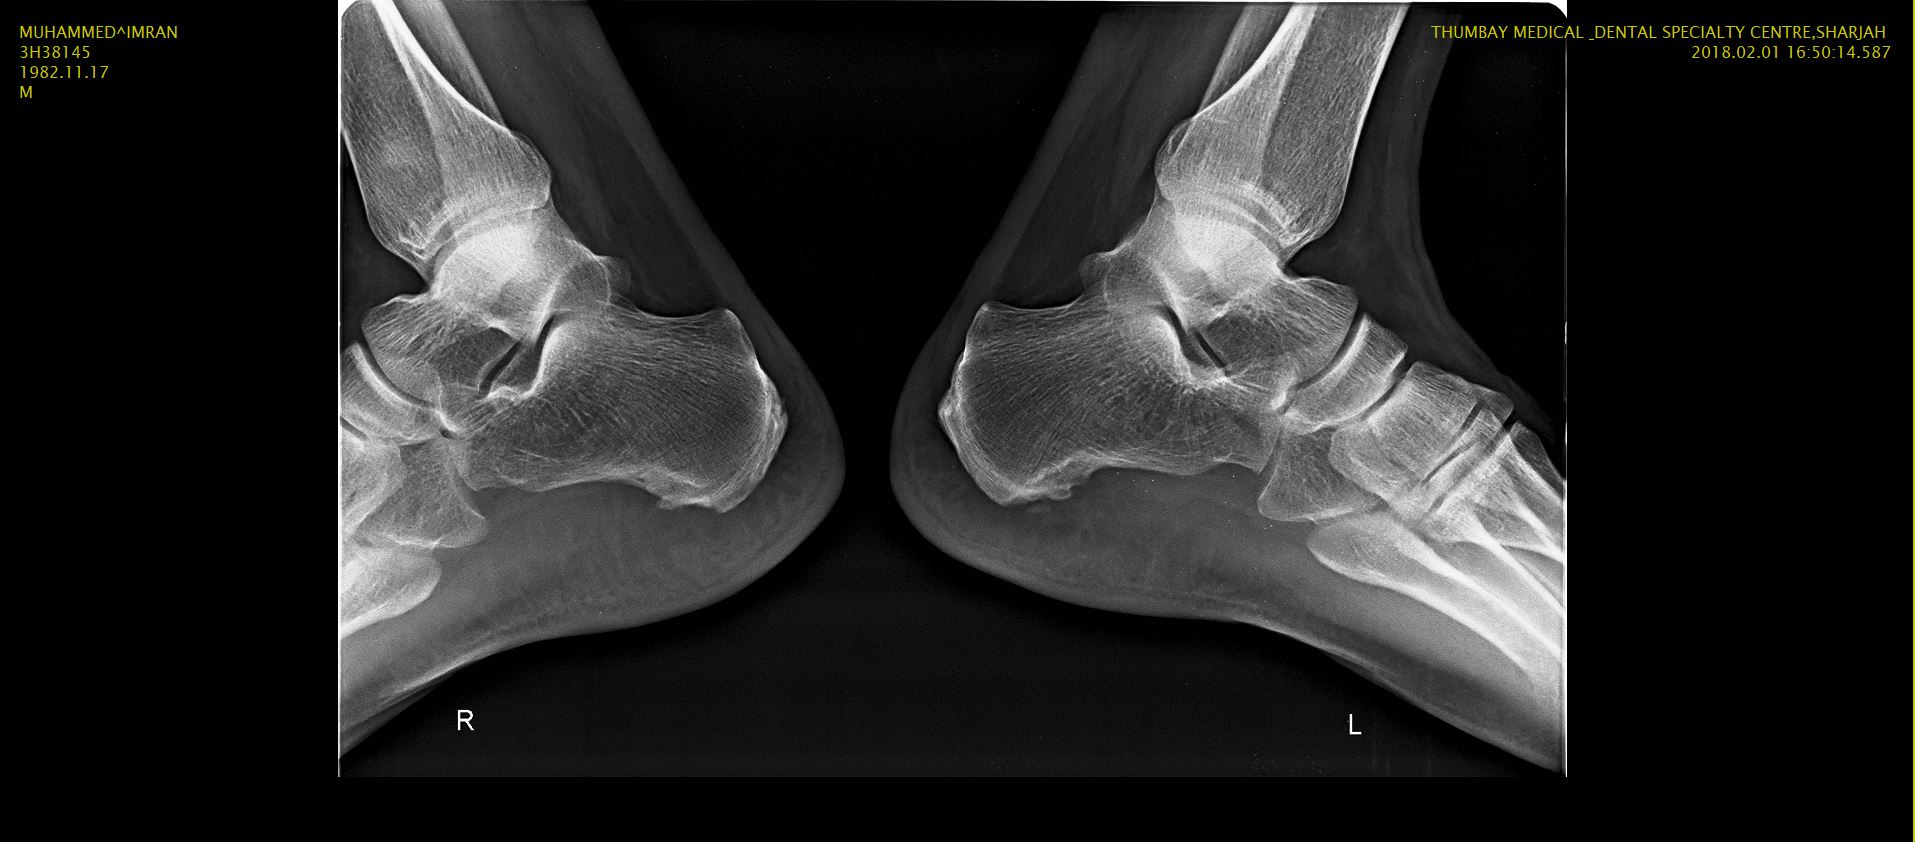

i am suffering PF pain for my both foot from last 3 years i took 4 times steroid injection & lot of pain killers tablets injections & some basic exercises but pain was same last November right foot Pf release surgery done in Multan Dr said left foot surgery after 6 months i came back here sharjah in January & from last week i am feeling pain left foot & as well right foot now after fresh X Ray & MRI here Dr diagnosed HEEL SPUR here Dr advised first physiotherapy i am going hospital daily for physiotherapy but still pain is same is there any permanent solution for this disease PF & HEEL SPUR kindly help me.